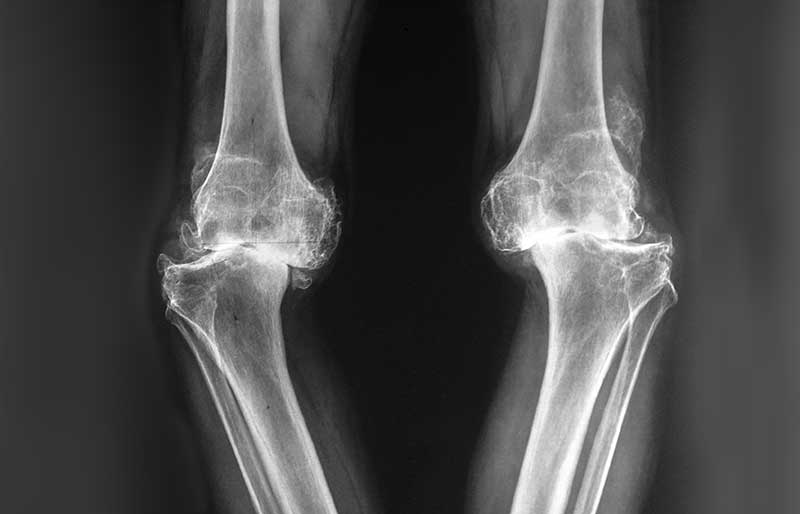

Osteoartritis (penipisan tulang rawan sendi) adalah suatu penyakit di mana tulang rawan mengalami kerusakan, penipisan dan akhirnya hilang sama sekali. Tulang rawan berfungsi melapisi ujung tulang pembentuk sendi agar tulang tidak saling bergesekan secara langsung, sehingga sendi dapat bergerak tanpa ham- batan dan rasa sakit. Osteoartritis adalah penyebab utama nyeri sendi, khususnya lutut dan panggul, pada orang berusia di atas 45 tahun. Osteoartritis sama sekali berbeda dengan osteoporosis (keropos tulang).

Kerusakan dan penipisan tulang rawan memicu terjadinya proses peradangan sendi (melalui terbentuknya beberapa zat kimia tertentu di dalam sendi), sehingga sendi terasa nyeri dan kadang-kadang membengkak. Jika penipisan semakin berat sehingga tulang rawan hilang sama sekali, maka ujung tulang pembentuk sendi saling bergesekan secara langsung sehingga menimbulkan rasa nyeri yang berat dan gangguan mekanis berupa bunyi “krek-krek” dan sendi menjadi kaku.

Pada stadium awal, keluhan penderita osteoartritis berupa nyeri dan kaku sendi setelah lama tidak bergerak; sebagai contoh, lutut terasa sakit dan kaku saat bangun tidur, saat berdiri dari posisi duduk atau saat turun dari mobil, atau saat berjongkok. Lutut juga terasa sakit jika digunakan naik atau turun tangga. Pada stadium yang lebih berat, lutut terasa sakit saat dipakai berjalan, terutama jika berjalan jauh. Sering terdengar bunyi “krek- krek” saat sendi digerakkan.